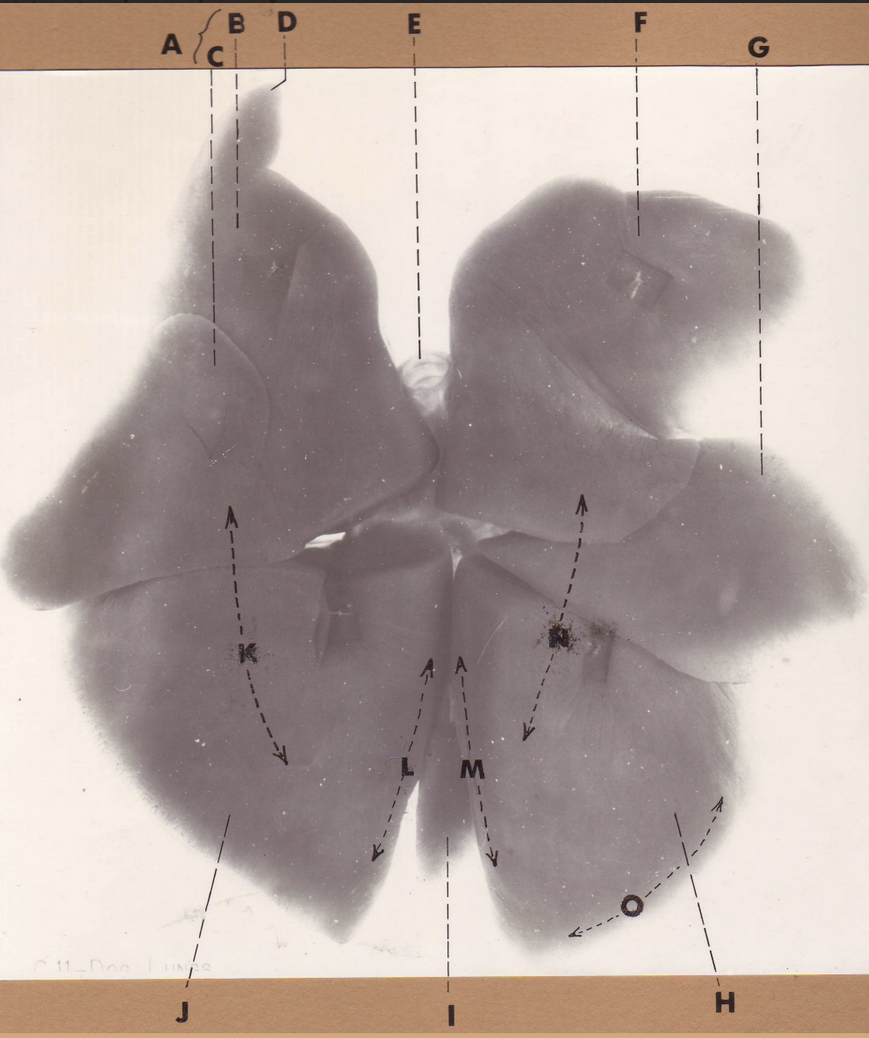

A

(cat larynx/trachea/lungs, dorsal)

epiglottis

B

(cat larynx/trachea/lungs, dorsal)

larynx

C

(cat larynx/trachea/lungs, dorsal)

trachea

D

(cat larynx/trachea/lungs, dorsal)

R cranial lobe

E

(cat larynx/trachea/lungs, dorsal)

middle lobe

F

(cat larynx/trachea/lungs, dorsal)

R caudal lobe

G

(cat larynx/trachea/lungs, dorsal)

primary bronchi

H

(cat larynx/trachea/lungs, dorsal)

L caudal lobe

I

(cat larynx/trachea/lungs, dorsal)

L cranial lobe

J

(cat larynx/trachea/lungs, dorsal)

cricoarytenoideus dorsalis m

K

(cat larynx/trachea/lungs, dorsal)

thyroid

A

(cat larynx/trachea/lungs, dorsal)

epiglottis

B

(cat larynx/trachea/lungs, dorsal)

larynx

C

(cat larynx/trachea/lungs, dorsal)

trachea

D

(cat larynx/trachea/lungs, dorsal)

R cranial lobe

E

(cat larynx/trachea/lungs, dorsal)

middle lobe

F

(cat larynx/trachea/lungs, dorsal)

R caudal lobe

G

(cat larynx/trachea/lungs, dorsal)

primary bronchi

H

(cat larynx/trachea/lungs, dorsal)

L caudal lobe

I

(cat larynx/trachea/lungs, dorsal)

L cranial lobe

J

(cat larynx/trachea/lungs, dorsal)

cricoarytenoideus dorsalis m

K

(cat larynx/trachea/lungs, dorsal)

thyroid